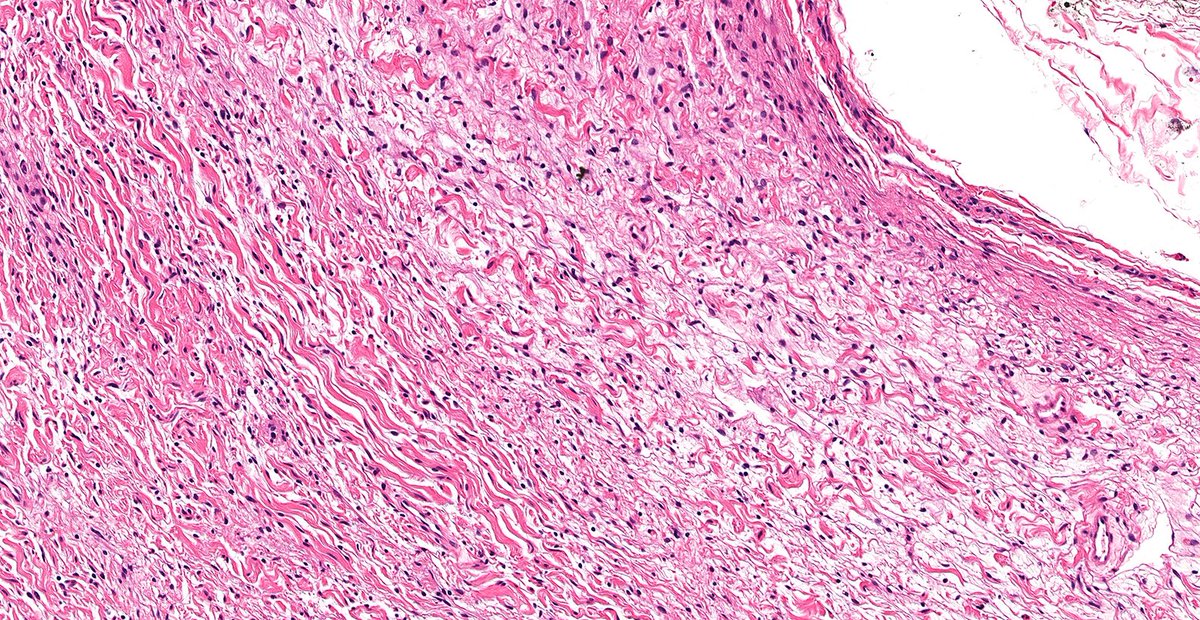

Let’s continue to review low-grade spindle cell lesions of breast this week! Case of Neurofibroma of Breast 🔬 Benign spindle cell lesion with wavy nuclei and collagen bundles—a reminder that not all breast spindle cell lesions are metaplastic. #PathX #PathTwitter #breastpath

Let’s continue to review low-grade spindle cell lesions of breast this week!

Case of Neurofibroma of Breast 🔬

Benign spindle cell lesion with wavy nuclei and collagen bundles—a reminder that not all breast spindle cell lesions are metaplastic.

#PathX #PathTwitter #breastpath